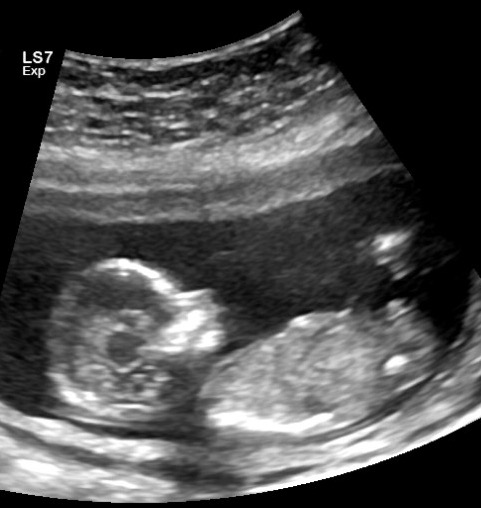

Hi Everyone! I'm just wondering if anyone can provide any insight on whether you think this Ultrasound at 14 weeks is a boy or girl. Thank you!! :)Attachment 32026Attachment 32027

I'm not sure if this is a potty shot. To be honest, all I know is that I'm looking at two legs. What do you think?

Definitely boy [emoji170]! In the previous pic of the potty shot, you can see a scrotum.